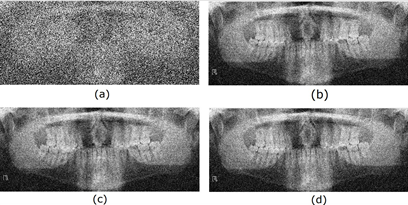

Finally, the radiological images restored using different adaptive filters are presented. Figures 6, 7, 8, and 9 show the noisy and restored images using different 2D adaptive filtering algorithms, respectively. From visual observation, it can be seen that the proposed filter produces a smoother version of the image and, thus, a slightly higher noise reduction compared to the LMS and 2D-NLMS algorithms. Furthermore, the proposed filter improves the visualization of the elements present in the image by more accurately highlighting transitions or edges. This enhancement means that details and structures of interest in the image become more discernible and can be appreciated with greater clarity.

Figure 3 shows the radiological images used for the simulation. These images are available in an open-source database [9]. The access path to the images is as follows: DentalPanoramicXrays.zip → Images → 1.png, 29.png, 58.png, 116.png.